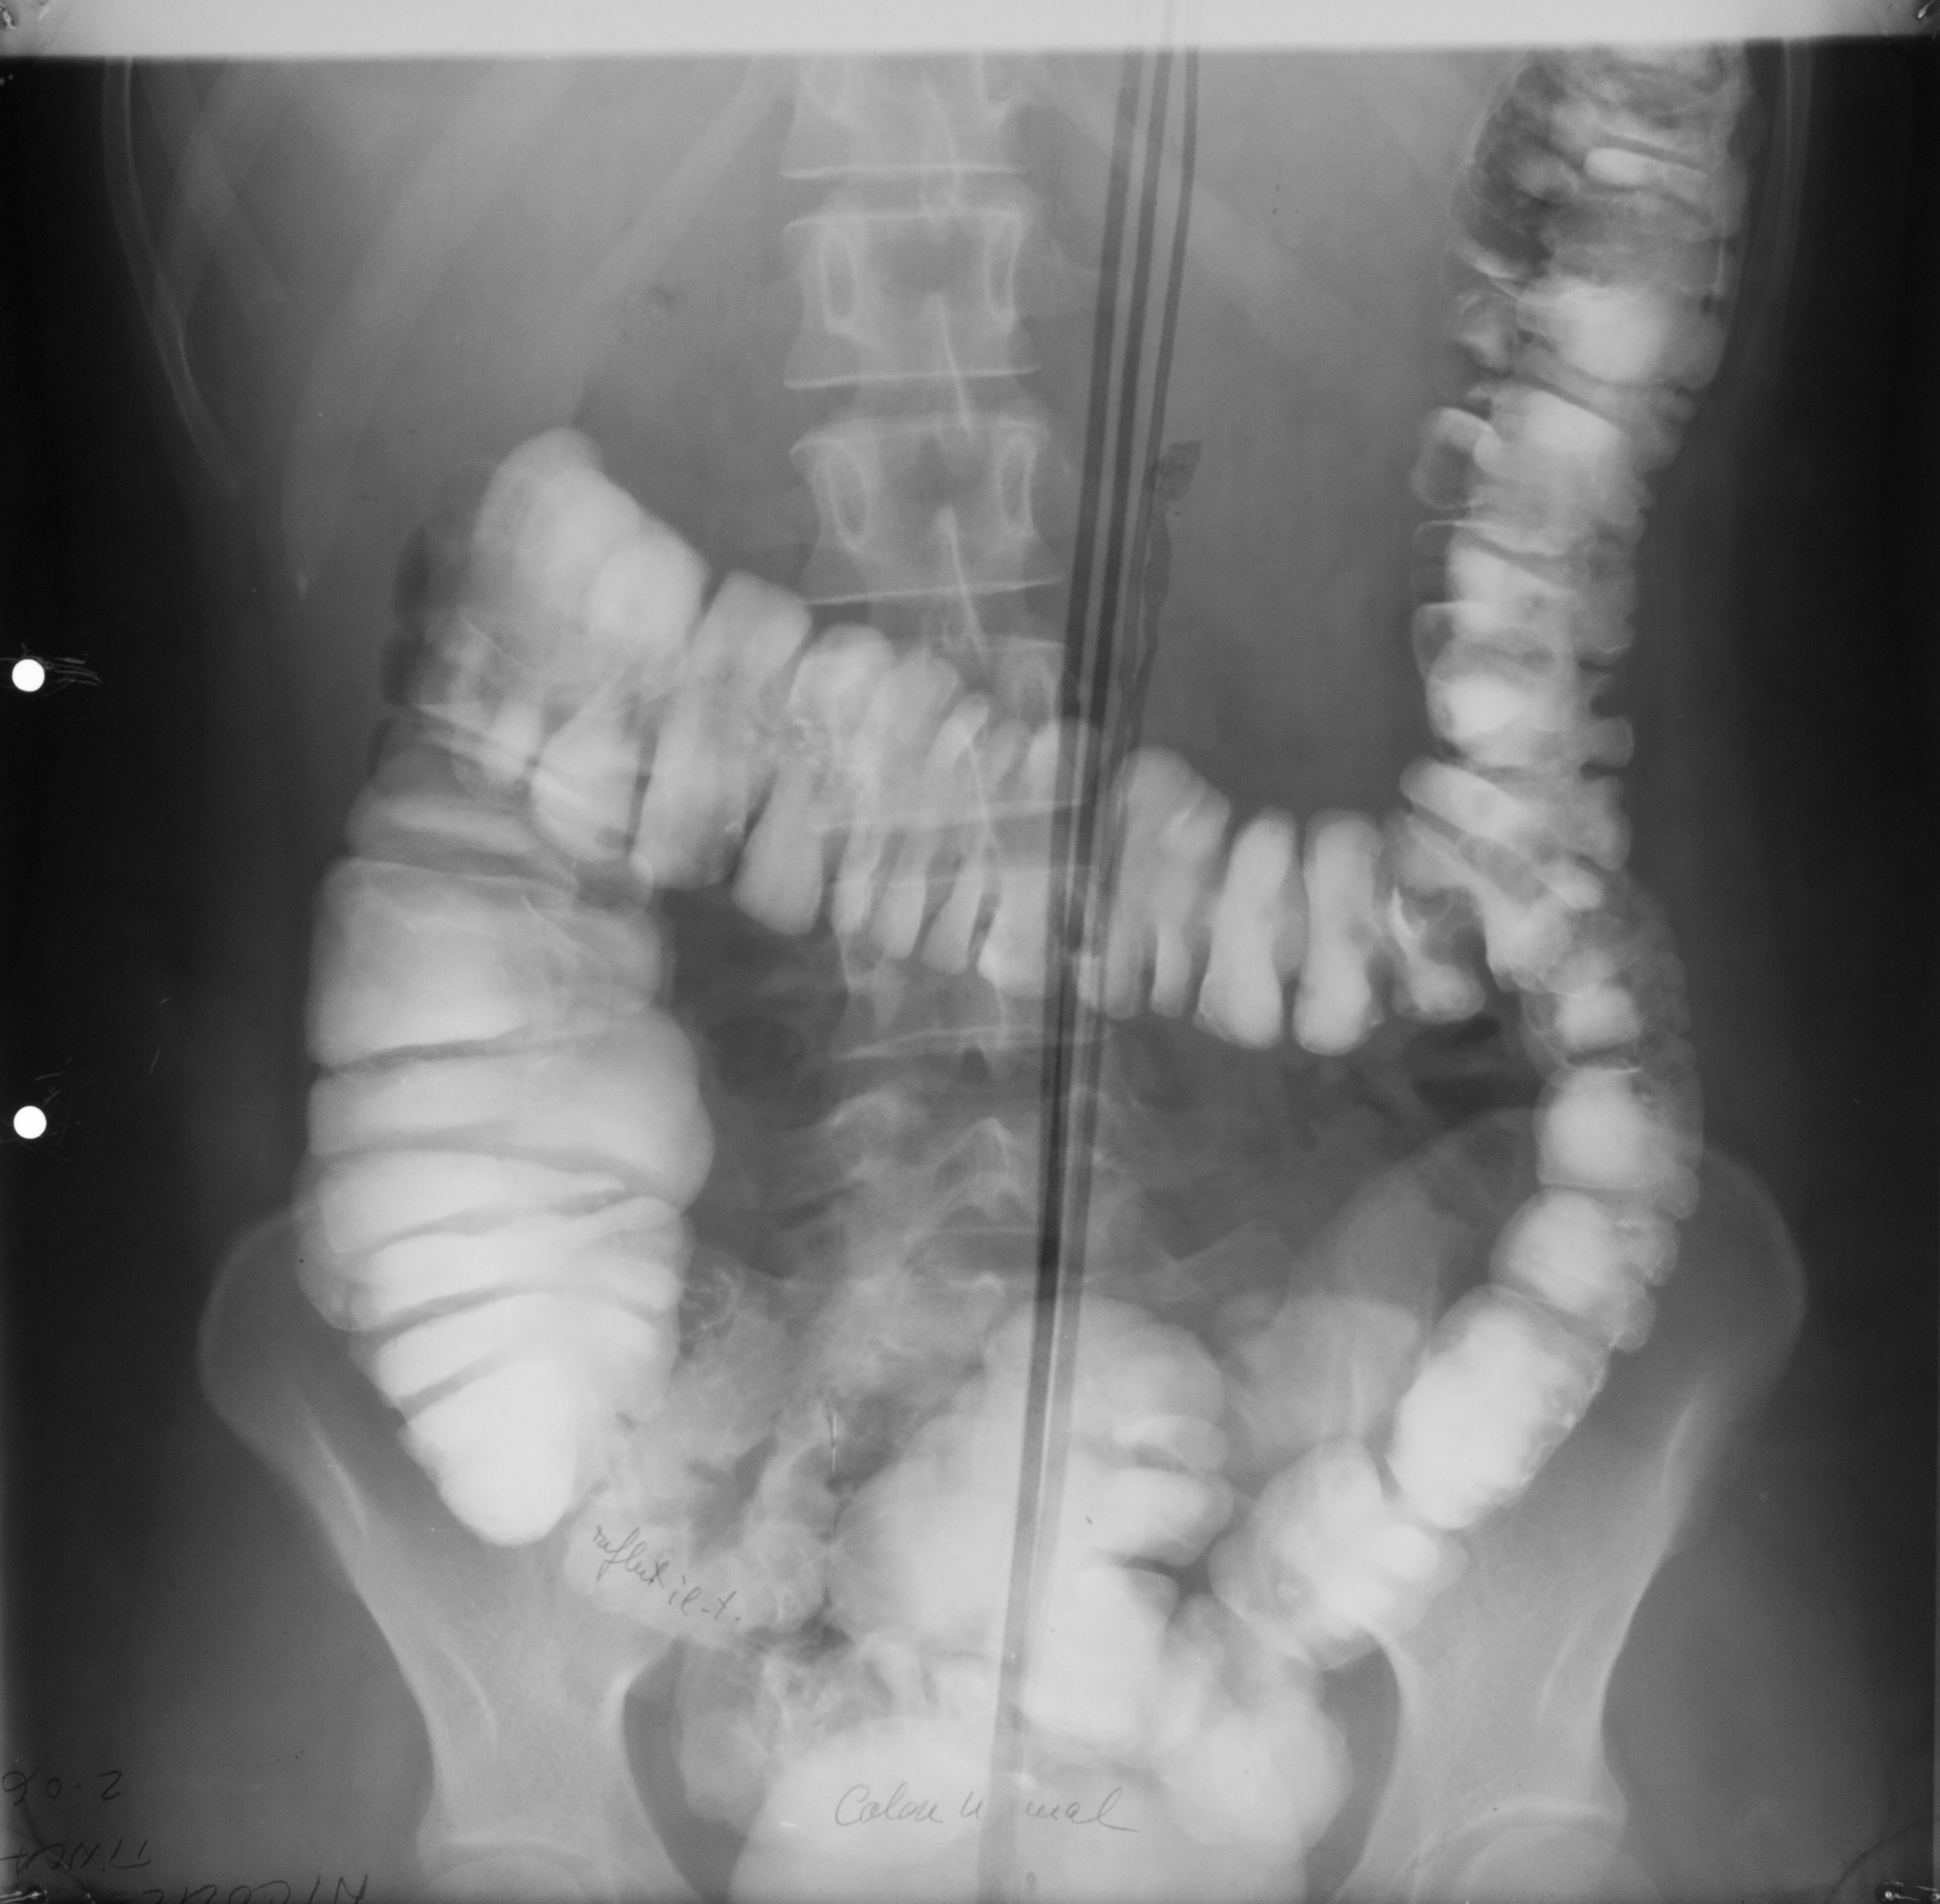

: IRIGOGRAFIE

Aspect radiologic al irigoscopiei unde recunoastem cec ascendent, flexura hepatica , transvers care este ptozat si e singura modificare care nu este neaparat patologica, flexura splenica, colon desccendent, sigmoid si rect. Absolut normal pentru persoana relativ in varsta

DEFECT DE UMPLERE (IRIGOSCOPIE/IRIGOGRAFIE)

Este rotund, bine net liniar delimitat, probabil ceva polip

DIVERTICULI (IRIGOGRAFIE)

Multiple imagini de aditie la nivelul cadrului colic

STENOZA MALIGNA = ADENOCARCINOM DE COLON

Tot irigografie cu zona de stenoza la nivelul colonului transvers, vedem coloana vertebrala si colon descendent, cu contur neregulat la extremitati, cu aspect de cotor de mar

Tot irigografie.

Zona de stenoza la nivelul colonului descendent si retrodilatatie cu aspect de pantalon de golf, proces infiltrativ la nivelul colonului. Mai putin frecvent decat adenocarcinomul

PROCES NEOPLAZIC CU STENOZĂ

Colon descendent, sigma, zona de stenoza fara mucoasa la nivelul acestei zone, proces neoplazic.

NEOPLASM

Aspect de cotor de mar cu stenoza, contur neregulat, retrodilatatii,lipsa lizereului de siguranță,deci lipsa mucoasei la acest nivel. Neoplasm